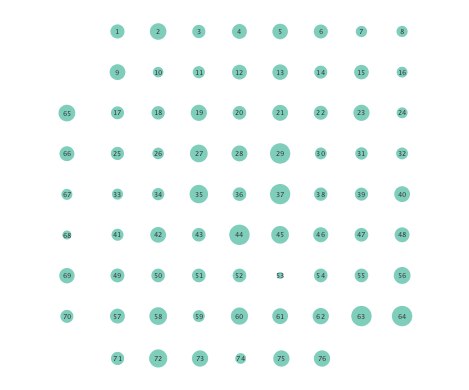

Clustering coefficients are generally used to quantify network cohesion, the tendency for nodes to form groups or communities. Comparison of such coefficients between the preictal and ictal phases may reveal differences in cohesive behavior after onset of a seizure. In the present paper, a per-node clustering coefficient is adopted, and it computes the fraction of triangles in which a node participates out of all possible triangles to which it could possibly belong [24]. Note that a triangle is defined as a fully connected three-node subgraph. Figure 5 depicts clustering coefficients per electrode obtained during the ictal and preictal phases of the ECoG time series. While both the linear and nonlinear models yield changes in the computed coefficients, most nodes have lower clustering coefficients upon seizure onset in the networks inferred via the K-SVARM.

Finally, Figure 6 depicts the closeness centrality computed per node in the inferred networks. Closeness centrality measures how reachable a node is from all other nodes, and is generally defined as the reciprocal of the sum of geodesic distances of the node from all other nodes in the network; see also [24]. Once again, Figure 6 depicts a more general decrease in closeness centralities after seizure onset in networks inferred by the nonlinear SVARM, as compared to the linear variant. This empirical result indicates a change in reachability between regions of the brain during an epileptic seizure.